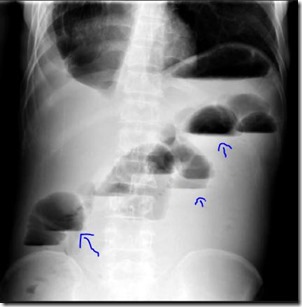

Intestinal perforation, on the other hand, is an emergency and it usually needs surgical intervention. in the image below, on the left side you see an erect abdominal X-ray and on the right-hand side, you see a chest X-Ray that shows intestinal perforation.The X-ray finding in case of intestinal obstruction is “air under diaphragm”. Air looks blackish in the X-Ray film. The arrows in both the X-Rays show air under the diaphragm. In the chest X-ray, it can be noticed easily that the blackish lungs and blackish air under the diaphragm are separated from each other by a thin whitish ridge of the diaphragm.